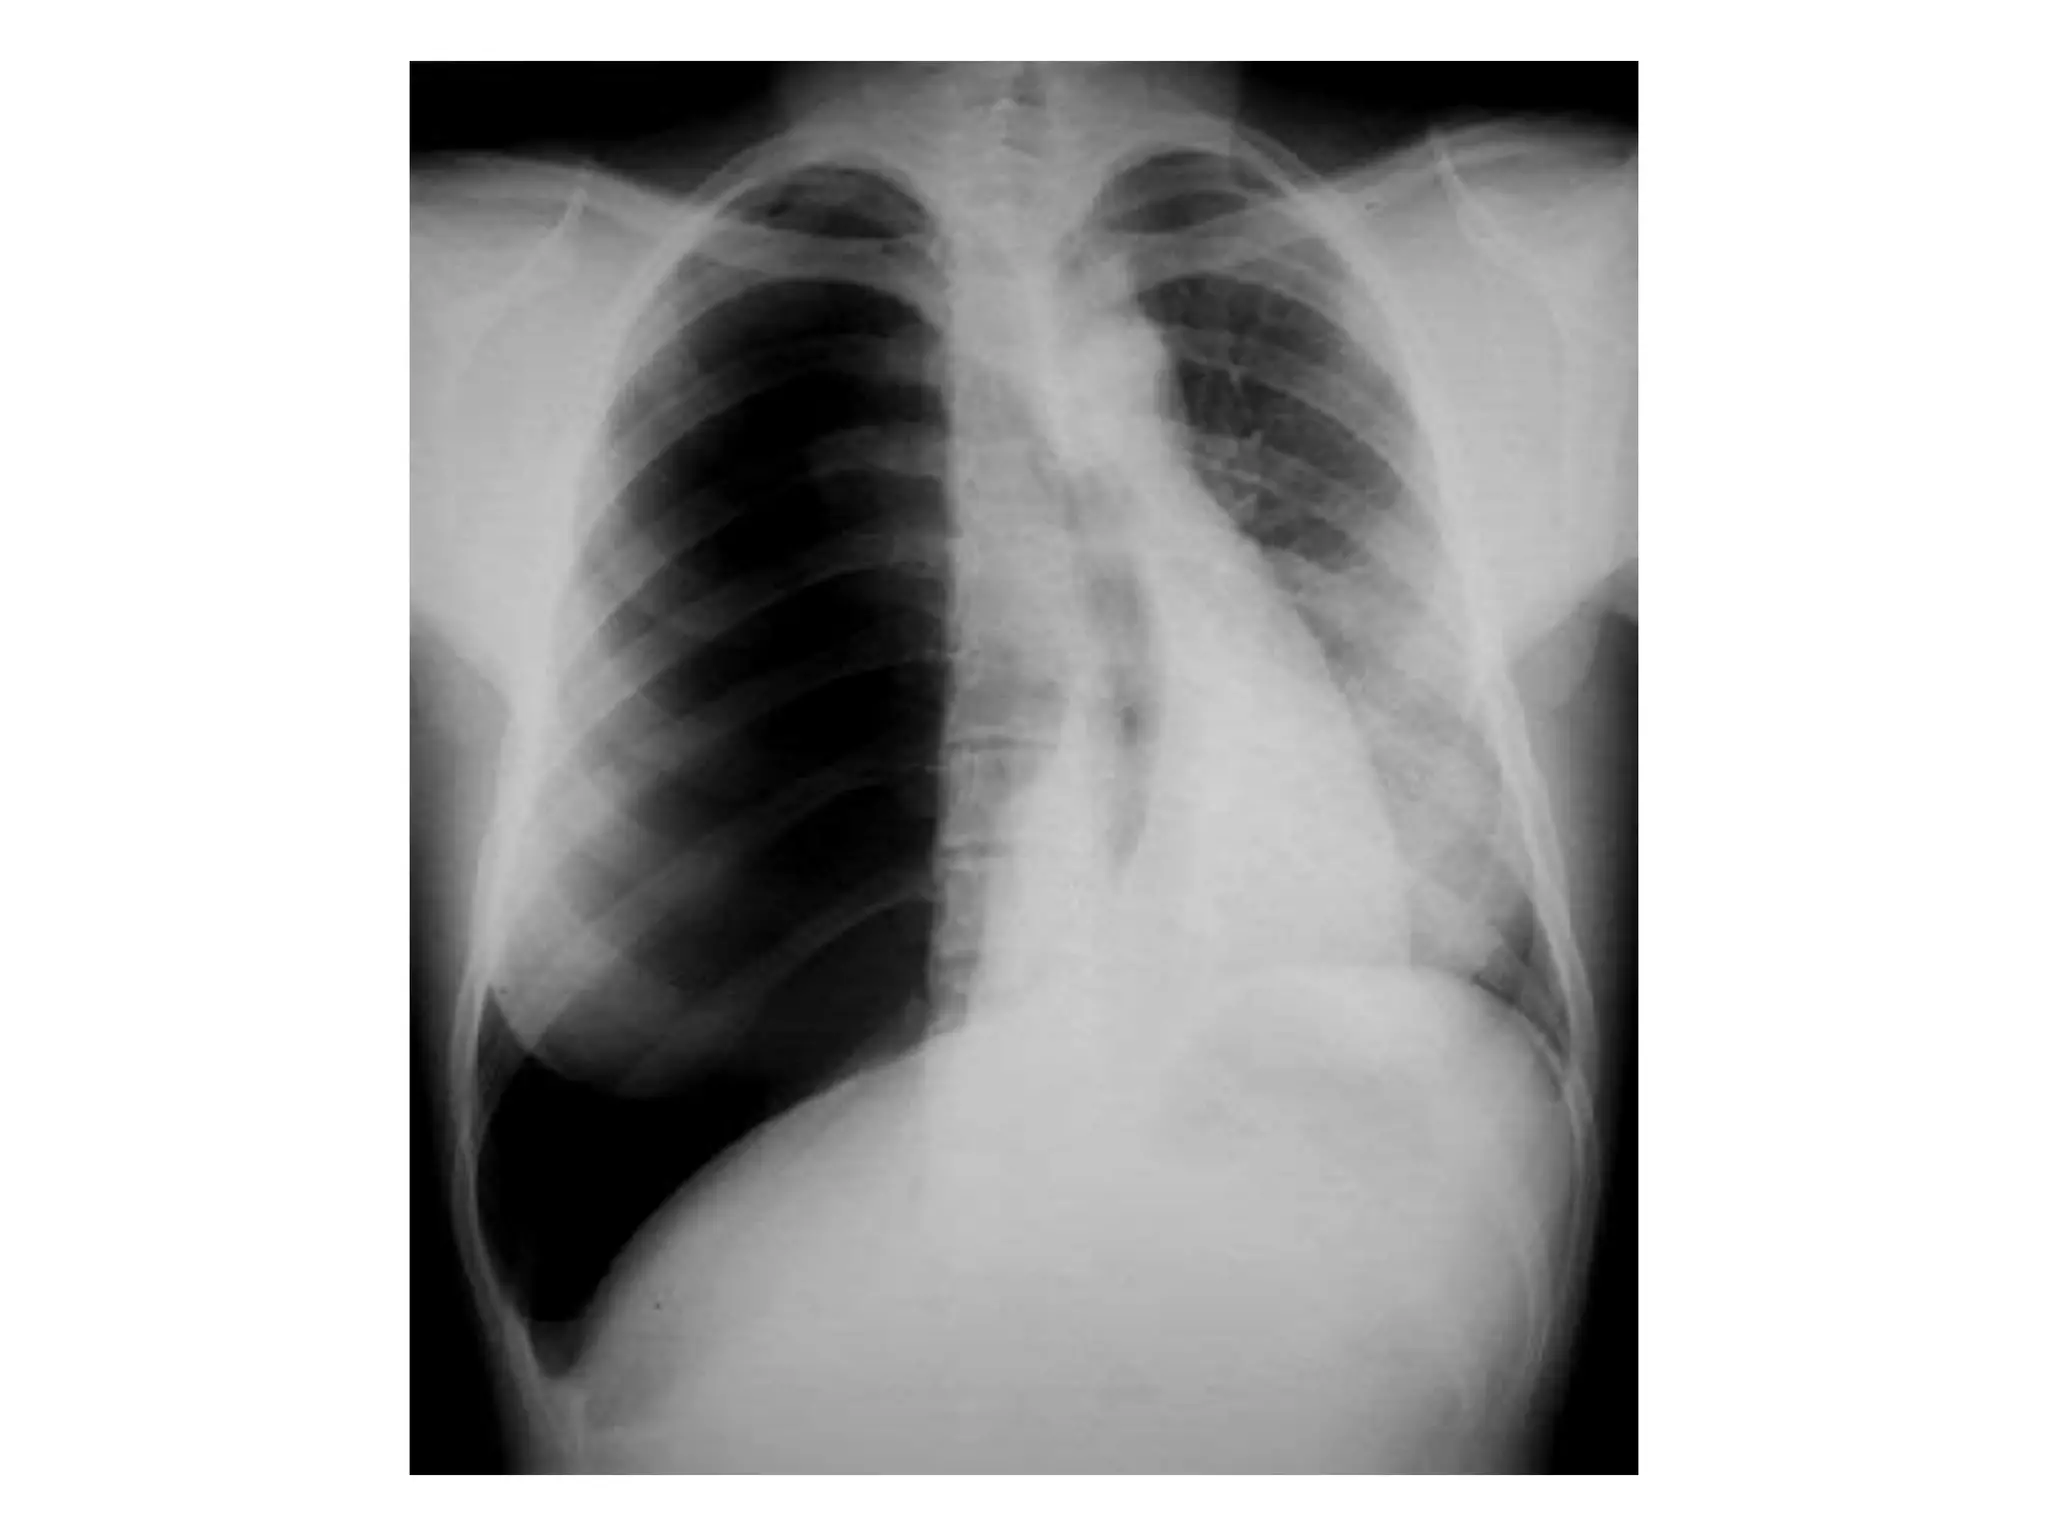

• Chest X-ray PA view showing trachea is

central, lung fields are clear, both hilum are

normal, mediastinum is normal, cardiac

shadow is normal in size and contour, both

costophrenic and cardiophrenic angles are

clear, diaphragm is normal in shape and

position, bony skeleton and soft tissue

shadows are normal.

The normal chestX-ray • Chest X-ray PA view showing trachea is central, lung fields are clear, both hilum are normal, mediastinum is normal, cardiac shadow is normal in size and contour, both costophrenic and cardiophrenic angles are clear, diaphragm is normal in shape and position, bony skeleton and soft tissue shadows are normal.